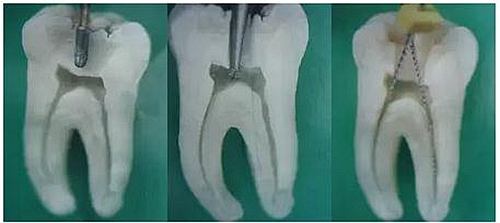

1.開髓:洞型是否制備的符合要求,髓室頂是否揭得剛剛好,沒有破壞洞壁及洞底結(jié)構(gòu)。

圖1裂鉆鉆到近髓 圖2球鉆穿髓 圖3小號銼探查根管口

圖4 球鉆揭髓頂 圖5修整洞型 圖6完成開髓